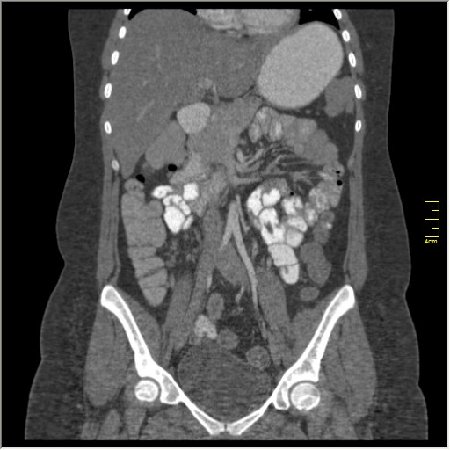

КТ энтерография

Демонстрационные изображение, оцените возможности метода! Толщина среза реконструкции 0.5-1 мм.